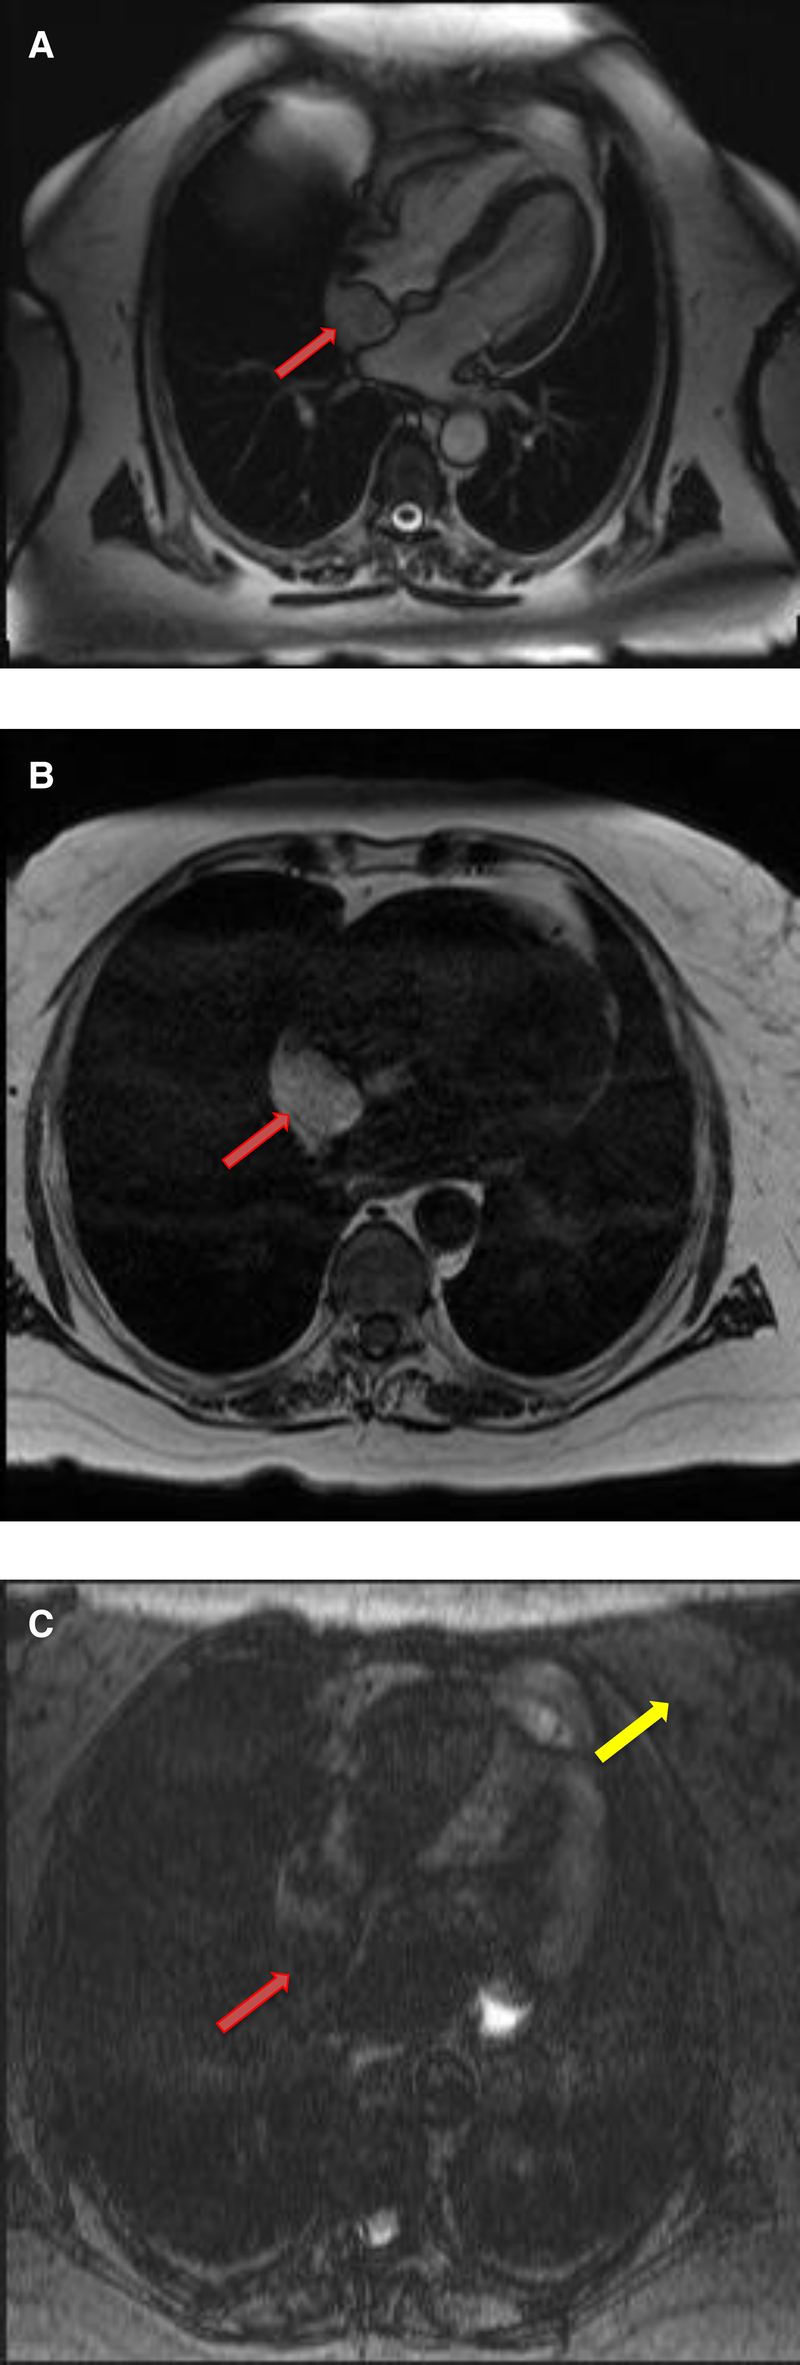

Cardiac myxomas typically have a heterogeneous appearance on CMR because of varying components of myxoid, cystic, hemorrhagic, fibrotic, and calcified material (27). As they are highly mobile tumors, cine imaging is often very helpful in the work-up of myxomas. Tumor mobility, including mitral valve prolapse causing obstruction, may be seen on the cine images. On SSFP cine sequences myxomas are usually hypointense relative to the blood pool and hyperintense relative to the myocardium (28). They are isointense/hypointense to the myocardium on T1- weighted images and hyperintense on T2-weighted images likely due to high extracellular water contents. There may be associated regions of necrosis and hemorrhage that appear hypointense on both T1- and T2-weighted images (29). Most of the myxomas demonstrate at least some mild patchy enhancement on the first pass perfusion images. Myxomas usually show moderate to high, heterogeneous enhancement on LGE images (Table 1 and Figures 3, 4). Occasionally myxomas may also exhibit a homogeneous enhancement pattern.

Figure 3

A 51-year-old female with left atrial myxoma. (A) Absence of perfusion of the lesion on first pass perfusion images (red arrow). (B) Following gadolinium administration, there is brisk, heterogeneous enhancement of this lesion on late gadolinium enhanced images (red arrow).

Figure 4

A 69-year-old female with right ventricular apical myxoma. (A) Localizer CMR images showing a small hyperintense mass in the distal RV (red arrow). (B) The mass showing high signal intensity on axial T2weighted, dark blood, double inversion recovery fast spin echo images (red arrow). (C) The mass shows absence of perfusion on first pass perfusion images (red arrow). (D) Heterogeneous enhancement of this lesion is noted on late gadolinium enhanced images. (E) There are small central areas of non-enhancement representing necrotic or hemorrhagic material (yellow arrow). RV, right ventricle.